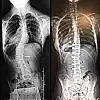

Omurilik ve Sinir Cerrahisi Uzmanı Opr. Dr. Ahmet Karkucak, skolyoz hastalığının nedenlerini, belirtilerini ve tedavi yöntemleri hakkında bilgiler verdi. Opr. Dr. Karkucak, "Skolyoz omurganın sevikal, trogal ve lomberde later dönüşleri ve rotasyonu ile seyreden omuriliğin kanal darlıklarına neden olabilen, iç organları özellikle akciğer ve kalp basılarına neden olabilen omurganın eğriliği olarak tarif edilebilecek bir hastalıktır. Kız çocuklarında ağırlıklı olarak daha sık bir şekilde görülen skolyoz, omurganın sağa ya da sol tarafa doğru eğilmesi neticesinde ortaya çıkan, kalça, göğüs kafesi ve kürek kemiklerini büyük oranda etkiler. Genellikle konzental olup altta yatan nedenler içinde omurganın gelişimi ile ilgili doğumsal efeklerin etki ettiği, patojenlerin beraber olabildiği bir omurga eğriliği durumudur. Sonradan olan omurga eğriliği skolyoz bu bir travma sonrası omurga da kemik kırıkları buna bağlı olarak değişiklikler olabilir” diye konuştu.

Skolyozun farklı sağlık sorunları oluşturabileceğini belirten Karkucak, “Omuzlardan birinin diğerine göre biraz daha yüksek olması yer alır. Omuzlar sağa ya da sola doğru kayma gösterebilir. Aynı durum bizzat kalça bölgesi için de geçerlidir. Bel girinti asimetrisi ve sırtta kaburgada yükseklik (çıkıntı) en önemli bulgularındandır. Öte yandan kürek kemiklerinin duruşunda da eşitlik açısından belli problemler ön plana çıkabilir. Skolyoz rahatsızlığına dair şüphe uyandıran bir bozukluk tespit edildiğinde vakit kaybetmeden bir hekime başvurulmalıdır. Skolyoz hangi aşamasında olursa olsun tedavi edilmediği takdirde çok daha başka sağlık sorunlarını beraberinde getirebilir” şeklinde konuştu.

“Erken tanı ve doğru tedavi seçimiyle skolyozun tam düzeltilmesi mümkündür. Tedavi ile yalnızca oluşan eğrilik düzeltilmez; bu eğriliğin neden olduğu şekil bozukluğuna bağlı olarak göğüs kafesinde meydana gelen hacim daralmasının da önüne geçilir. Skolyozda cerrahiye karar verilmeden önce en önemli etken skolyozun açısı, hastanın yaşı, genel durumu olarak görüntüsü, skolyoza bağlı olarak kalp, akciğer gibi solunum sıkıntısına neden olabilecek bası bulguları belirler. Burada tanı konulduktan sonra çok vakit kaybetmeden yakın takibe alıp önce egzersizler en önemli olan yüzme omurganın eğriliğini düzeltmek için tedaviye başlanmalıdır."